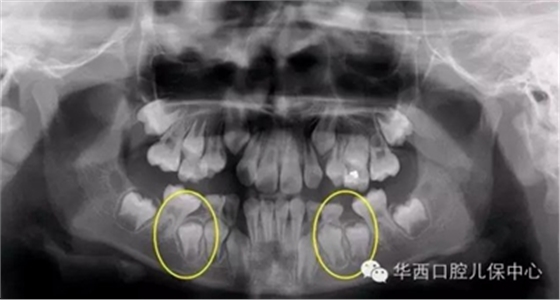

圖為下頜乳磨牙早失,未行間隙管理,繼承恒牙無(wú)法萌出(黃圈內(nèi))